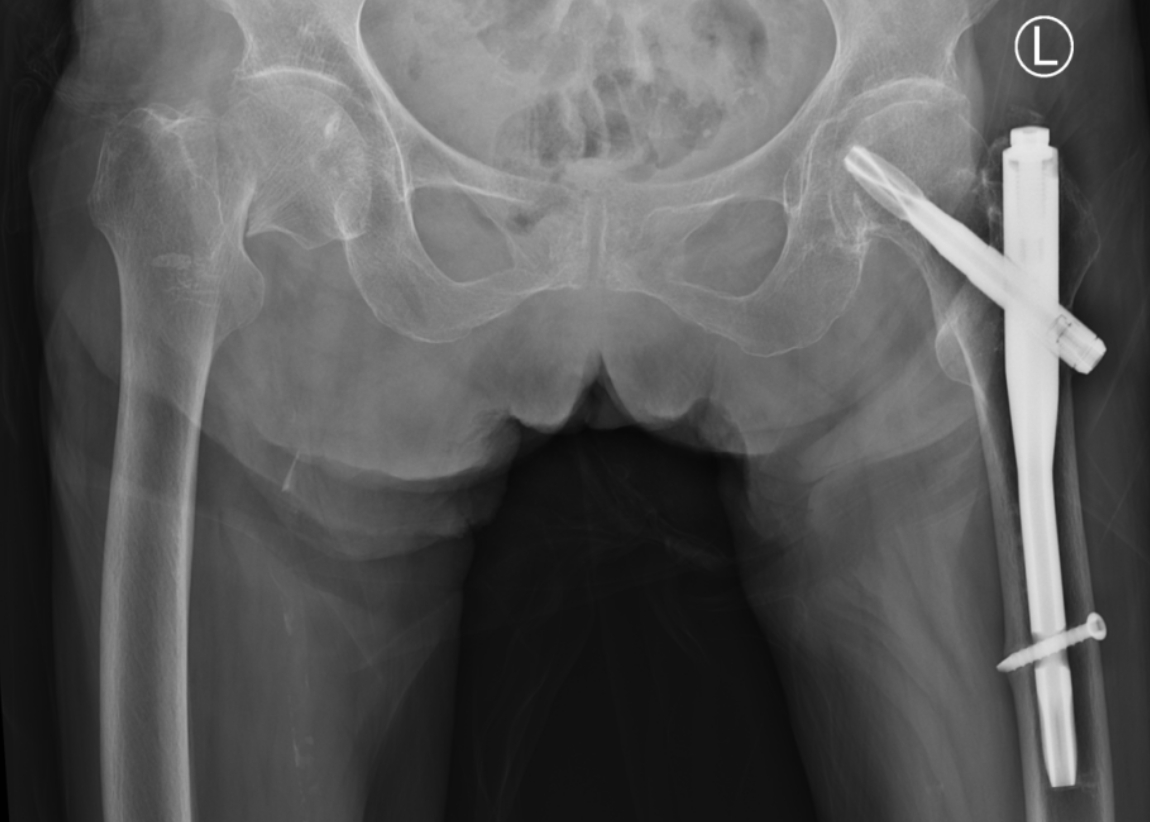

术后

术后,顺利康复,石奶奶重新行走、生活自理。